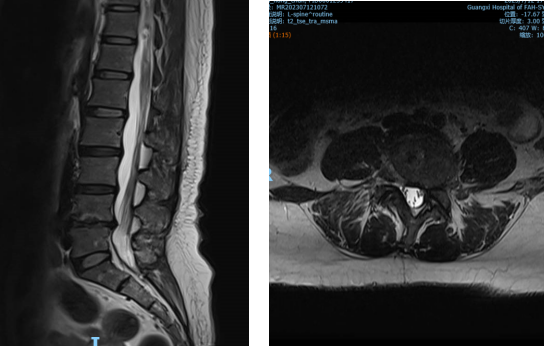

▲②术前MRI片

“医生,我这半年来腰痛的厉害,右腿现在又痛又麻,走路都困难,有什么办法处理吗?”在骨科诊室,患者谭阿姨(化名)苦恼地说道。中山一院广西医院骨科脊柱外科专业专家欧裕福副主任医师详细询问谭阿姨病史,并为她安排了细致的检查,最终诊断为腰椎管狭窄症+腰椎滑脱症。

术后第一天,医生为谭阿姨伤口换药并为他进行了腰椎X线及CT复查,显示手术后内固定植入物固定良好,椎间融合器放置在位,下肢麻木及疼痛症状明显好转。经过一系列的康复锻炼,谭阿姨术后第二天下床行走,术后5天办理出院。